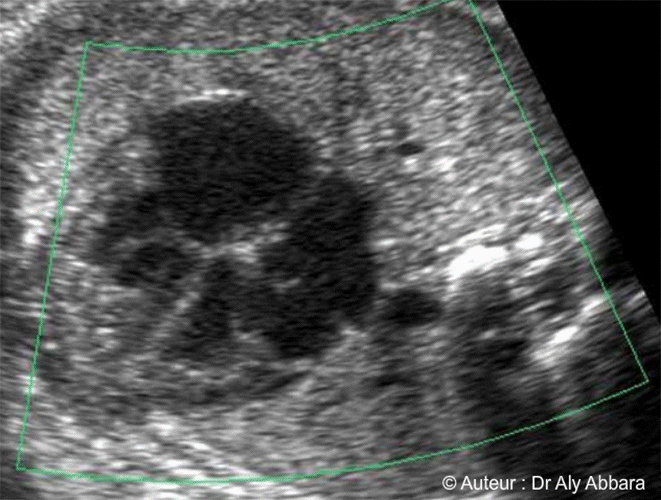

Image échographique mettant en évidence les quatre veines pulmonaires fœtales

grâce au Doppler couleur (Dynamic-Flow).